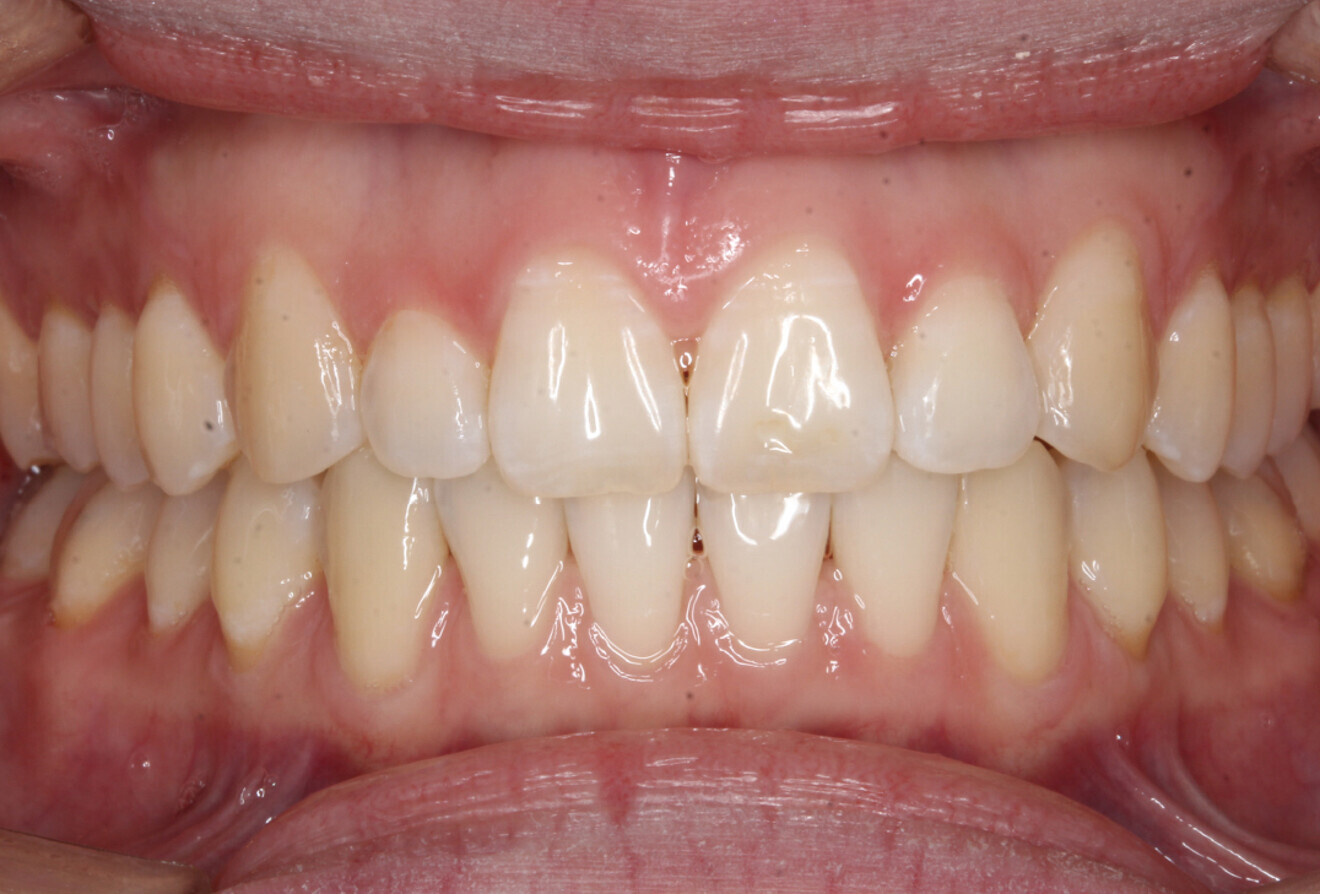

Fig. 4f: Frontal intra-oral view.

Advantages of mandibular repositioning therapy

In this case example, by using the S8-SGTB appliance, extraction of the maxillary second premolars was avoided. After mandibular advancement therapy, anti-clockwise rotation of the patient’s mandible was achieved. The morphology of the patient’s mandible was changed from a high angle to a normal angle. The patient’s mandibular retrusion and facial prognathism were improved and her joint clicking problem and joint pressure relieved. The overall treatment duration was much shortened.